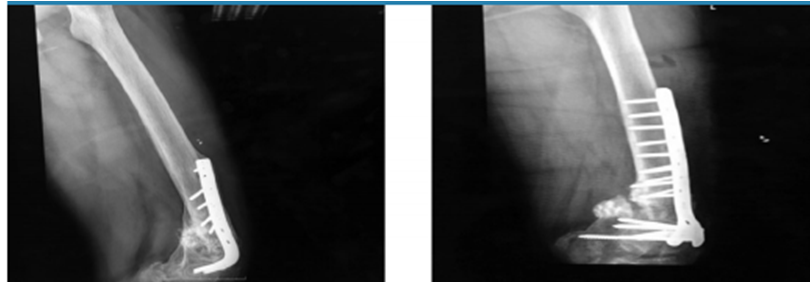

· 3 pacientes con fracturas de tercio distal de fémur supraintercondíleas con gran defecto óseo, para las cuales se utilizó placa condilar bloqueada en todas, se usó en un paciente 30 cc de aloinjerto de chip de esponjosa y en 2 aloinjerto de 60 cc de chip esponjosa (Fig. 2 y 3).

· 5 pacientes con pseudoartrosis, 3 correspondientes a meseta tibial a quienes se realizó osteosíntesis con placa de soporte en L y aloinjerto de chip de esponjosa 50 cc, 2 de fémur distal resueltas con placa condilar bloqueada con 60 cc de chip esponjosa y un paciente con fatiga de material de osteosíntesis (Fig. 4 y 5).